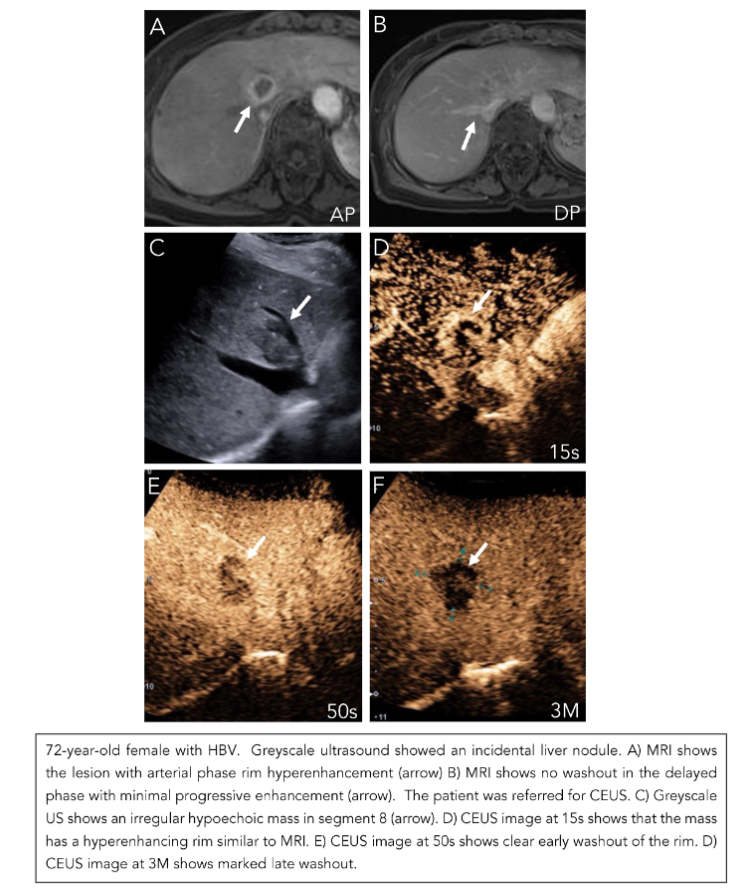

Any new nodule suspicious for HCC on greyscale US based on the LI-RADS US necessitates further multiphase contrast enhanced imaging with either MR, CT, or CEUS. HCC presents with a characteristic hemodynamic enhancement pattern of arterial phase hyperenhancement (APHE) and late mild washout in the delayed phases(15,16). Beyond creating a standardized reporting system, the LI-RADS framework is an accurate probabilistic model with the objective of providing a non-invasive means of specifically diagnosing HCC. Through a five-category classification system, it grades observed lesions using specific criteria to be “definitely benign” (LI-RADS 1) to “definitely HCC” (LI-RADS 5)(16). This results in a clear reporting system with high inter-observer reliability for the clinical team to base their management decisions on. For example, the designation of LI-RADS 5 given to a nodule greater than 1 cm with APHE and late and weak washout does not require a biopsy for a definite diagnosis (Figure 1). There are two time points that we keep in mind when looking for washout relative to time zero, which is when the microbubble contrast is flushed with normal saline. Any washout that occurs prior to 1 minute is considered early or rapid and consistent with non-hepatocellular malignancies. Washout that is marked and occurs by 2 minutes, is also indicative of a malignant non-HCC lesion. Additionally, care needs to be taken when interpreting APHE on CT and MRI in cirrhotic livers because they may represent pseudolesions such as nontumorous arterioportal shunts (Figure 2)(19).

These pseudolesions can be evaluated with US as a problem-solving tool to determine the presence of a true nodule and then characterize its enhancement and washout pattern(20). When we consider lesions that are “probably HCC” (LI-RADS 4), a biopsy is warranted as the incidence of HCC has been shown to be 48% in a study of 175 nodules (Figure 3)(18). This threshold to biopsy is informed by the specificity of the LI-RADS 5 criteria, which is supported by a meta-analysis of fourteen studies showing a pooled per-observation specificity of 91% (95% CI, 89%–93%)(21). Another important category to consider is LI-RADS M (malignancy), which describes a lesion to be “probably or definitely malignant,” but not necessarily in keeping with HCC(16). These lesions may exhibit a characteristic rim of APHE or early washout (less than 1 minute) or marked washout within 2 minutes. Any of these features will classify the lesion as LI-RADS M. Pathologies within this category can include metastases, intrahepatic cholangiocarcinoma (ICC), or in a minority of cases, benign lesions. The prospective identification of metastases or ICC, the second most common malignancy found in patients with chronic liver disease, is of the utmost importance as management strategies and prognosis differ between these pathologies and HCC(22). Alongside these non-HCC lesions, pathological correlation has interestingly shown 28.2% (95% CI, 23.8%–33.1%) of LI-RADS M lesions to ultimately be HCC (Figure 4). This is in part due to the stringent criteria set forth for a LI-RADS 5 lesion and the considerably higher incidence of HCC compared to pathologies like ICC(23). Overall, LI-RADS has been shown to be an effective framework for risk stratifying hepatic lesions concerning for increased risk of HCC.

Although LI-RADS was originally validated with CT and MRI, CEUS has similarly been shown to be an accurate imaging method for categorization of liver nodules(24). In a multi-center prospective study, CEUS of 545 nodules with confirmed reference standards demonstrated LI-RADS 5 to have a specificity of 95.1% (95% CI, 94.5%–98.7%)(24). These contrast-based imaging evaluations broadly share similar criteria given the intrinsic enhancement and washout patterns observed in HCC. However, these imaging modalities mutually share challenges in characterizing focal liver lesions like HCC when the liver parenchyma has undergone diffuse fatty changes. Our experience and literature have suggested that although APHE is usually preserved, it is difficult to appreciate washout properties of HCC on MRI with increasing steatosis(25). This absent washout may be secondary to increased background liver hypointensity in fatty liver, which gives the relative appearance of persistent enhancement or isoenhancement when trying to characterize washout in the delayed phase(26). Our experience has shown that CEUS can perform well in identifying nodules and their APHE in fatty liver but can be misleading when assessing for washout in the late phases. We believe this is because of the augmented surrounding enhancement in the late phases caused by the fat, which can portray a picture of “pseudowashout” (Figure 5). Short interval follow-up, repeat injection with a high frequency transducer, and consideration of liver specific contrast enhanced MR are warranted in these situations. Moreover, there is a critical difference that differentiates CEUS from CT/MRI when considering LI-RADS M lesions. In cases of ICC, CEUS and CT/MRI both show APHE, but in the portal venous phase, CEUS shows rapid washout whereas CT/MRI show progressive enhancement (Figure 6)(27). This discordance is thought to be secondary to the purely intra-vascular nature of microbubbles used in CEUS, which is unique compared to the recognized interstitial phase of iodinated and gadolinium-based contrast agents. Although this has yet to be considered in formulating the criteria for LI-RADS M lesions, this finding may further improve the accuracy of CEUS in the diagnosis of focal liver masses.